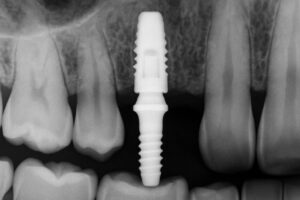

Teeth implants are small titanium posts placed in the jaw to serve as a tooth root. A crown, bridge, or denture is attached to that post to replace missing teeth. Many people search for “teeth implants near me in Denver, CO” because implants feel and function more like natural teeth than removable options.

Implant placement is often outpatient. The implant integrates with bone over weeks to months (osseointegration). After healing, an abutment and final crown or bridge are attached. Follow post-op care, avoid smoking, and keep good oral hygiene to support healing.